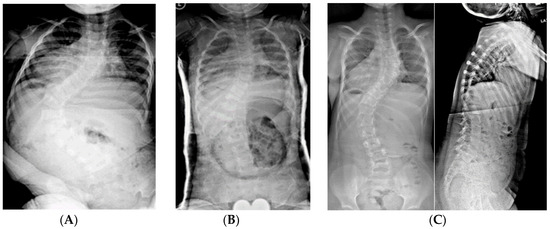

Figure 3.

(A) 19-month-old male with PWS deletion type with 52° curve. (B) Same patient at 20 months old, sitting in his first spinal cast, 10° curve in cast. (C) Same patient at 35 months old, after completing 8 casts, 11° curve. (D) Same patient at 6 years old, 3 years out of cast and 2 years out of brace, with an 18° curve.

Figure 4.

(A) 18-month-old female with PWS deletion type with 106° curve. (B) Same patient at 18 months old, sitting in first cast, 54° curve. (C) AP and lateral views of spine at 6 years old, after 18 casts, 61° curve, just prior to surgery. (D) AP and lateral views of spine 4 months after placing magnetically actuated spine rods T3–L3. Curve was corrected to 30°, maintaining her pre-operative kyphosis. (E) AP and lateral views of spine at 10 years old, just prior replacement with new expandable rods. Due to adding on, curve measures 50°, which was addressed by including L4 in the construct.